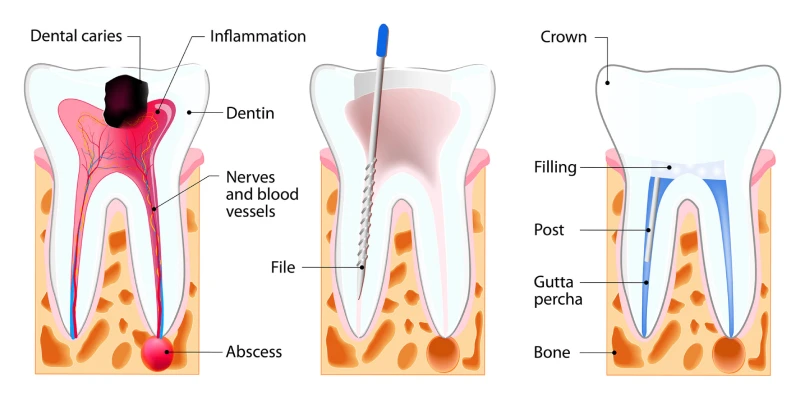

- Thorough Diagnosis: We perform digital X-rays and pulp vitality tests to determine the exact nature of the pain and assess the health of the tooth.

- Canal Cleaning: The infected part is cleared away, and the channels are sanitised to ease pain.

- Shaping & Sealing: Rotary instruments shape canals before sealing them against reinfection.

- Tooth Restoration: A crown strengthens the treated tooth, restoring natural function.

Endodontic therapy removes infection, disinfects the canals, seals them, and rebuilds the tooth with lasting protection.